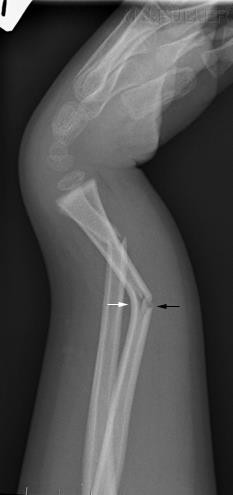

- Cơ chế chấn thương trực tiếp: Chấn thương với một tác nhân mạnh, trực tiếp vào chi, gây nên một tổn thương nặng: xương gãy phức tạp, phần mềm dập nát, đứt mạch máu và thần kinh ( tai nạn giao thông).

- Cơ chế chấn thương gián tiếp: Xương hay bị gãy chéo xoắn, phần mềm bị tổn thương nhẹ hơn ( gãy trên lồi cầu xương cánh tay ở trẻ em do ngã chống tay…)

Hình : Biến dạng trục chi do gãy xương